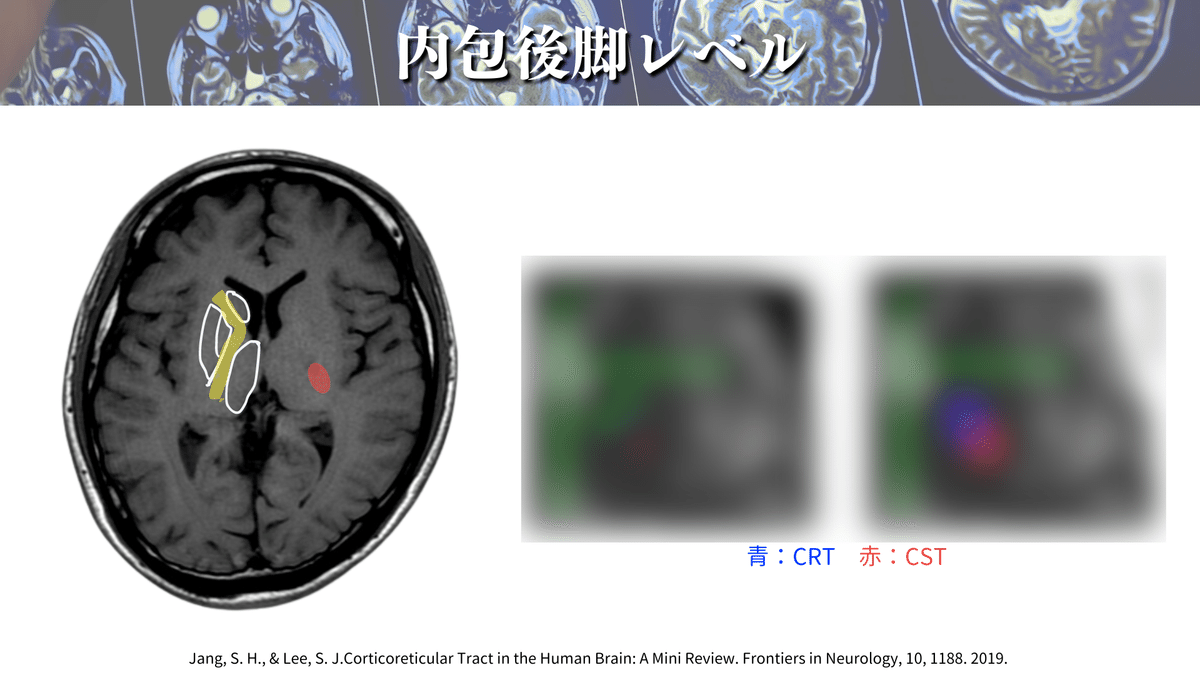

解像度を上げて見てみると、、、🔍

口顔の部分の運動線維の皮質延髄路は、内包膝を通って下降していきます👄

つまり、内包後脚部分を通るのは上下肢・体幹のCSTになるということですね✋🦶